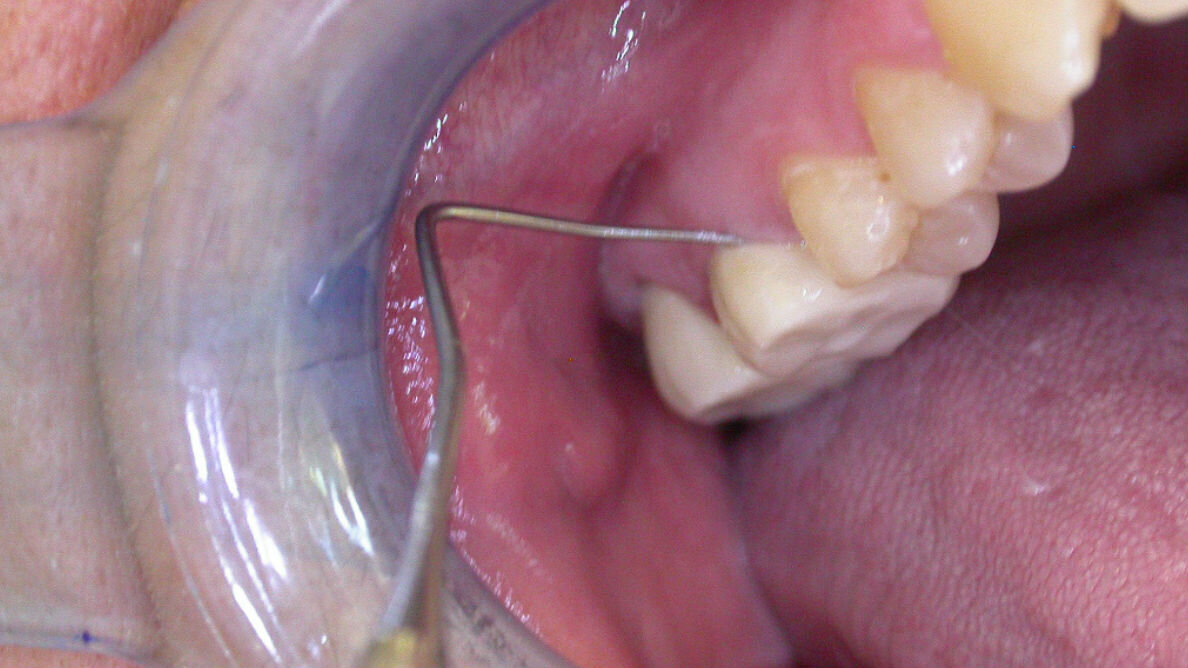

Luca esagera nel monconizzare il dente, ma soprattutto per errore “affetta” il 2.7, dente in precedenza integro, che diviene fortemente sensibile. Lucia avverte il caldo e il freddo, ha disturbi nella masticazione e percepisce la forma mutata del dente 2.7 (appiattito). Chiede spiegazioni a Mario e Luca, che dapprima negano il problema, ma che alla fine, allorquando Lucia ha evidenza di quanto accaduto da un altro odontoiatra, ammettono di aver “pelato leggermente” il dente retrostante. Negano, tuttavia, che la possibilità della dichiarata forte sensibilità, soprattutto termica, possa essere attribuita a tale “banalità” e non intervengono in alcun modo al fine di ridurre il disagio della loro paziente. Lucia, persa ogni fiducia in Mario, l’abbandona, desiderando la risoluzione del problema algico che la tormenta sempre più e che si trasforma in dolore costante. Mario indispettito propone decreto ingiuntivo al fine di ottenere il pagamento di una corona protesica, mai provata, mai realizzata e mai finalizzata, ma a suo dire pronta. A Lucia non rimane che opporsi, volente o nolente, al decreto ingiuntivo. Per Mario, Luca e Lucia inizia, per pochi spiccioli, un iter che condurrà non si sa quando e non si sa come a scontentare tutti. Mario e Luca risponderanno di quanto hanno mal controllato o eseguito e Lucia non sarà mai soddisfatta della ragione eventualmente ottenuta.